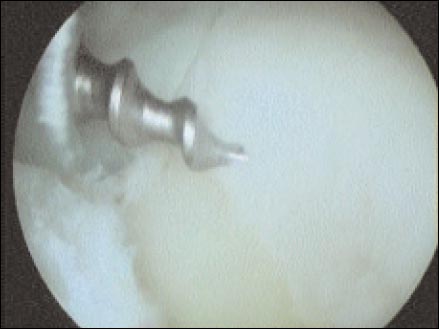

Los anclajes óseos son colocados en la unión oteocartilaginosa (Fig. 5) sobre el cartílago en tres puntos, aproximadamente correspondiente a horas 5, 4 y 2 (hombro derecho), dependiendo de la lesión; realizamos la toma capsular y del rodete con Ethibond Nº. 2, el pasaje de los hilos requiere de un “shutter-relay” o otros tipos de pasa-suturas. Utilizamos nudos deslizantes o no deslizantes según necesidad y, un empujanudos para llevar las estructuras capsulo-ligamentarias al sitio deseado.(Fig. 6). Con ambas técnicas realizamos plicaturas capsulares con los mismos puntos de la sutura transglenoidea o los anclajes óseos.

Figura 5: colocacion cartilaginosa